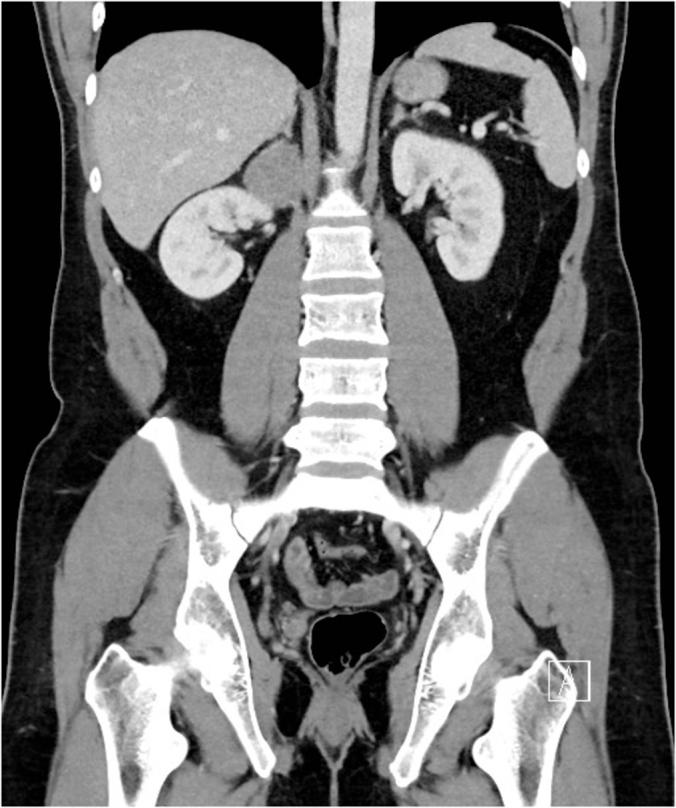

伪装成肾上腺皮质肿瘤的神经鞘瘤:一例报告并文献复习

Schwannoma masquerading as adrenocortical tumor: A case report and review of literature.

Schwannomas arises from retroperitoneal space are rare tumors. Adrenal Schwannomas are often misdiagnosed due to deficient of distinctive radiological findings. We report a case of adrenal schwannoma presented with vague abdominal pain. Initially, the patient was diagnosed as adrenocortical tumor that was treated with robotic adrenalectomy. Histopathological and immuno-histochemical examination revealed schwannoma. We will report the case and review the literature regarding this rare tumor.

摘要

起源于腹膜后间隙的神经鞘瘤是罕见肿瘤。肾上腺神经鞘瘤常因缺乏独特的影像学表现而被误诊。我们报告一例以腹部隐痛为表现的肾上腺神经鞘瘤病例。最初,该患者被诊断为肾上腺皮质肿瘤并接受了机器人辅助肾上腺切除术。组织病理学和免疫组织化学检查显示为神经鞘瘤。我们将报告该病例并复习有关这种罕见肿瘤的文献。